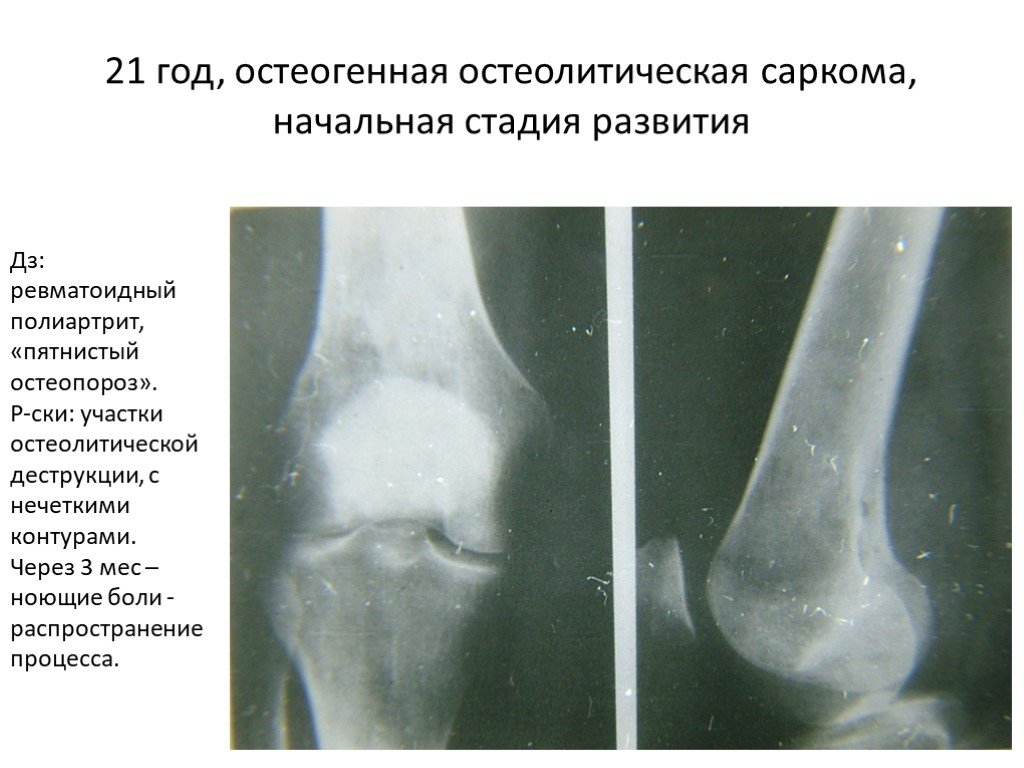

Рентгенологическая картина остеогенной саркомы кости - 98 фото